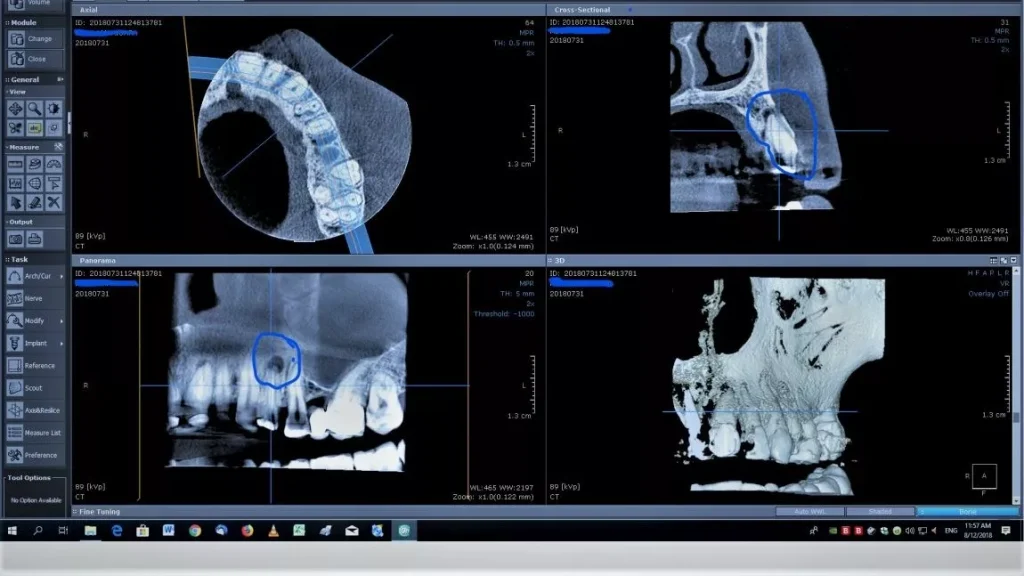

Comparativ cu radiografia panoramică, tomografia dentară 3D este cea mai precisă și eficientă metodă de diagnostic folosită astăzi.

Rezultatele sunt generate în format tridimensional, ceea ce permite o analiză detaliată și exactă.

Localizarea structurilor anatomice, măsurarea arcadelor, detectarea rapidă a leziunilor și identificarea formațiunilor anormale sunt doar câteva dintre avantajele tehnologiei 3D.

În implantologie, siguranța inserării depinde de măsurătorile tridimensionale și de simulările efectuate înainte de intervenție.

Un alt exemplu: identificarea mărimii unui granulom. În funcție de dimensiunea lui, tratamentul poate fi endodontic sau chirurgical.